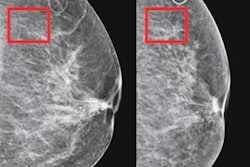

Further workup of mammograms within the top 20% of scores assigned to women by the Mirai risk model could result in over 40% of interval cancers being found, wrote a team led by Fiona Gilbert, MD, from the University of Cambridge in England.

Gilbert and colleagues studied Mirai’s ability to identify women who developed interval cancers in the U.K. breast screening program. The program invites women aged 50 to 70 years for triennial mammography. The researchers highlighted that breast screening programs could be better employed by improving the selection criteria for women who could benefit from supplemental imaging.

The team also had Mirai predict interval cancers for women assigned the highest 1%, 5%, 10%, and 20% of three-year risk scores. It found that Mirai predicted 3.6%, 14.5%, 26.1%, and 42.4% of interval cancers for these scores, respectively. Identifying the interval cancers is equivalent to an additional cancer detection rate of 0.1, 0.6, 1, and 1.7 per 1,000 exams.